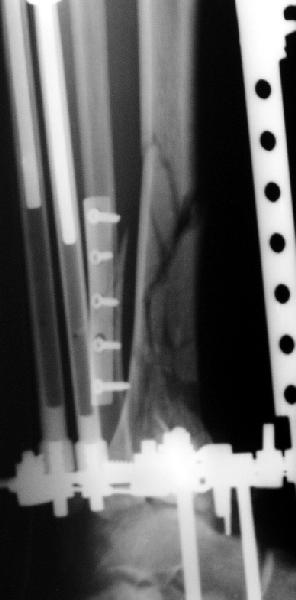

Мне кажется, что все дискутирующие согласным с одним - надо воостанавливать в данной ситуации суставную поверхность. Сделать это закрыто (когда суставная поверхность состит из 3-фрагментов)лично для меня не реально. Конечно можно открыто отрепонировать, зафиксировать спицами и оставить в аппарате, но роль аппарата и выполняет LSP. Разрез в области внутренней поверхность голеностопного сустава и небольшой разрез в ср/3 голени для проксимальных винтов, надкостница не обдирается, пластина вводится подкожно.

Вид конечности на следующий день после операции.

Наверно не дошел, вот еще раз.

8.jpg

14KB (14977 bytes)